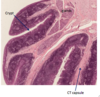

what is depicted in the image

Lymphoid tissue